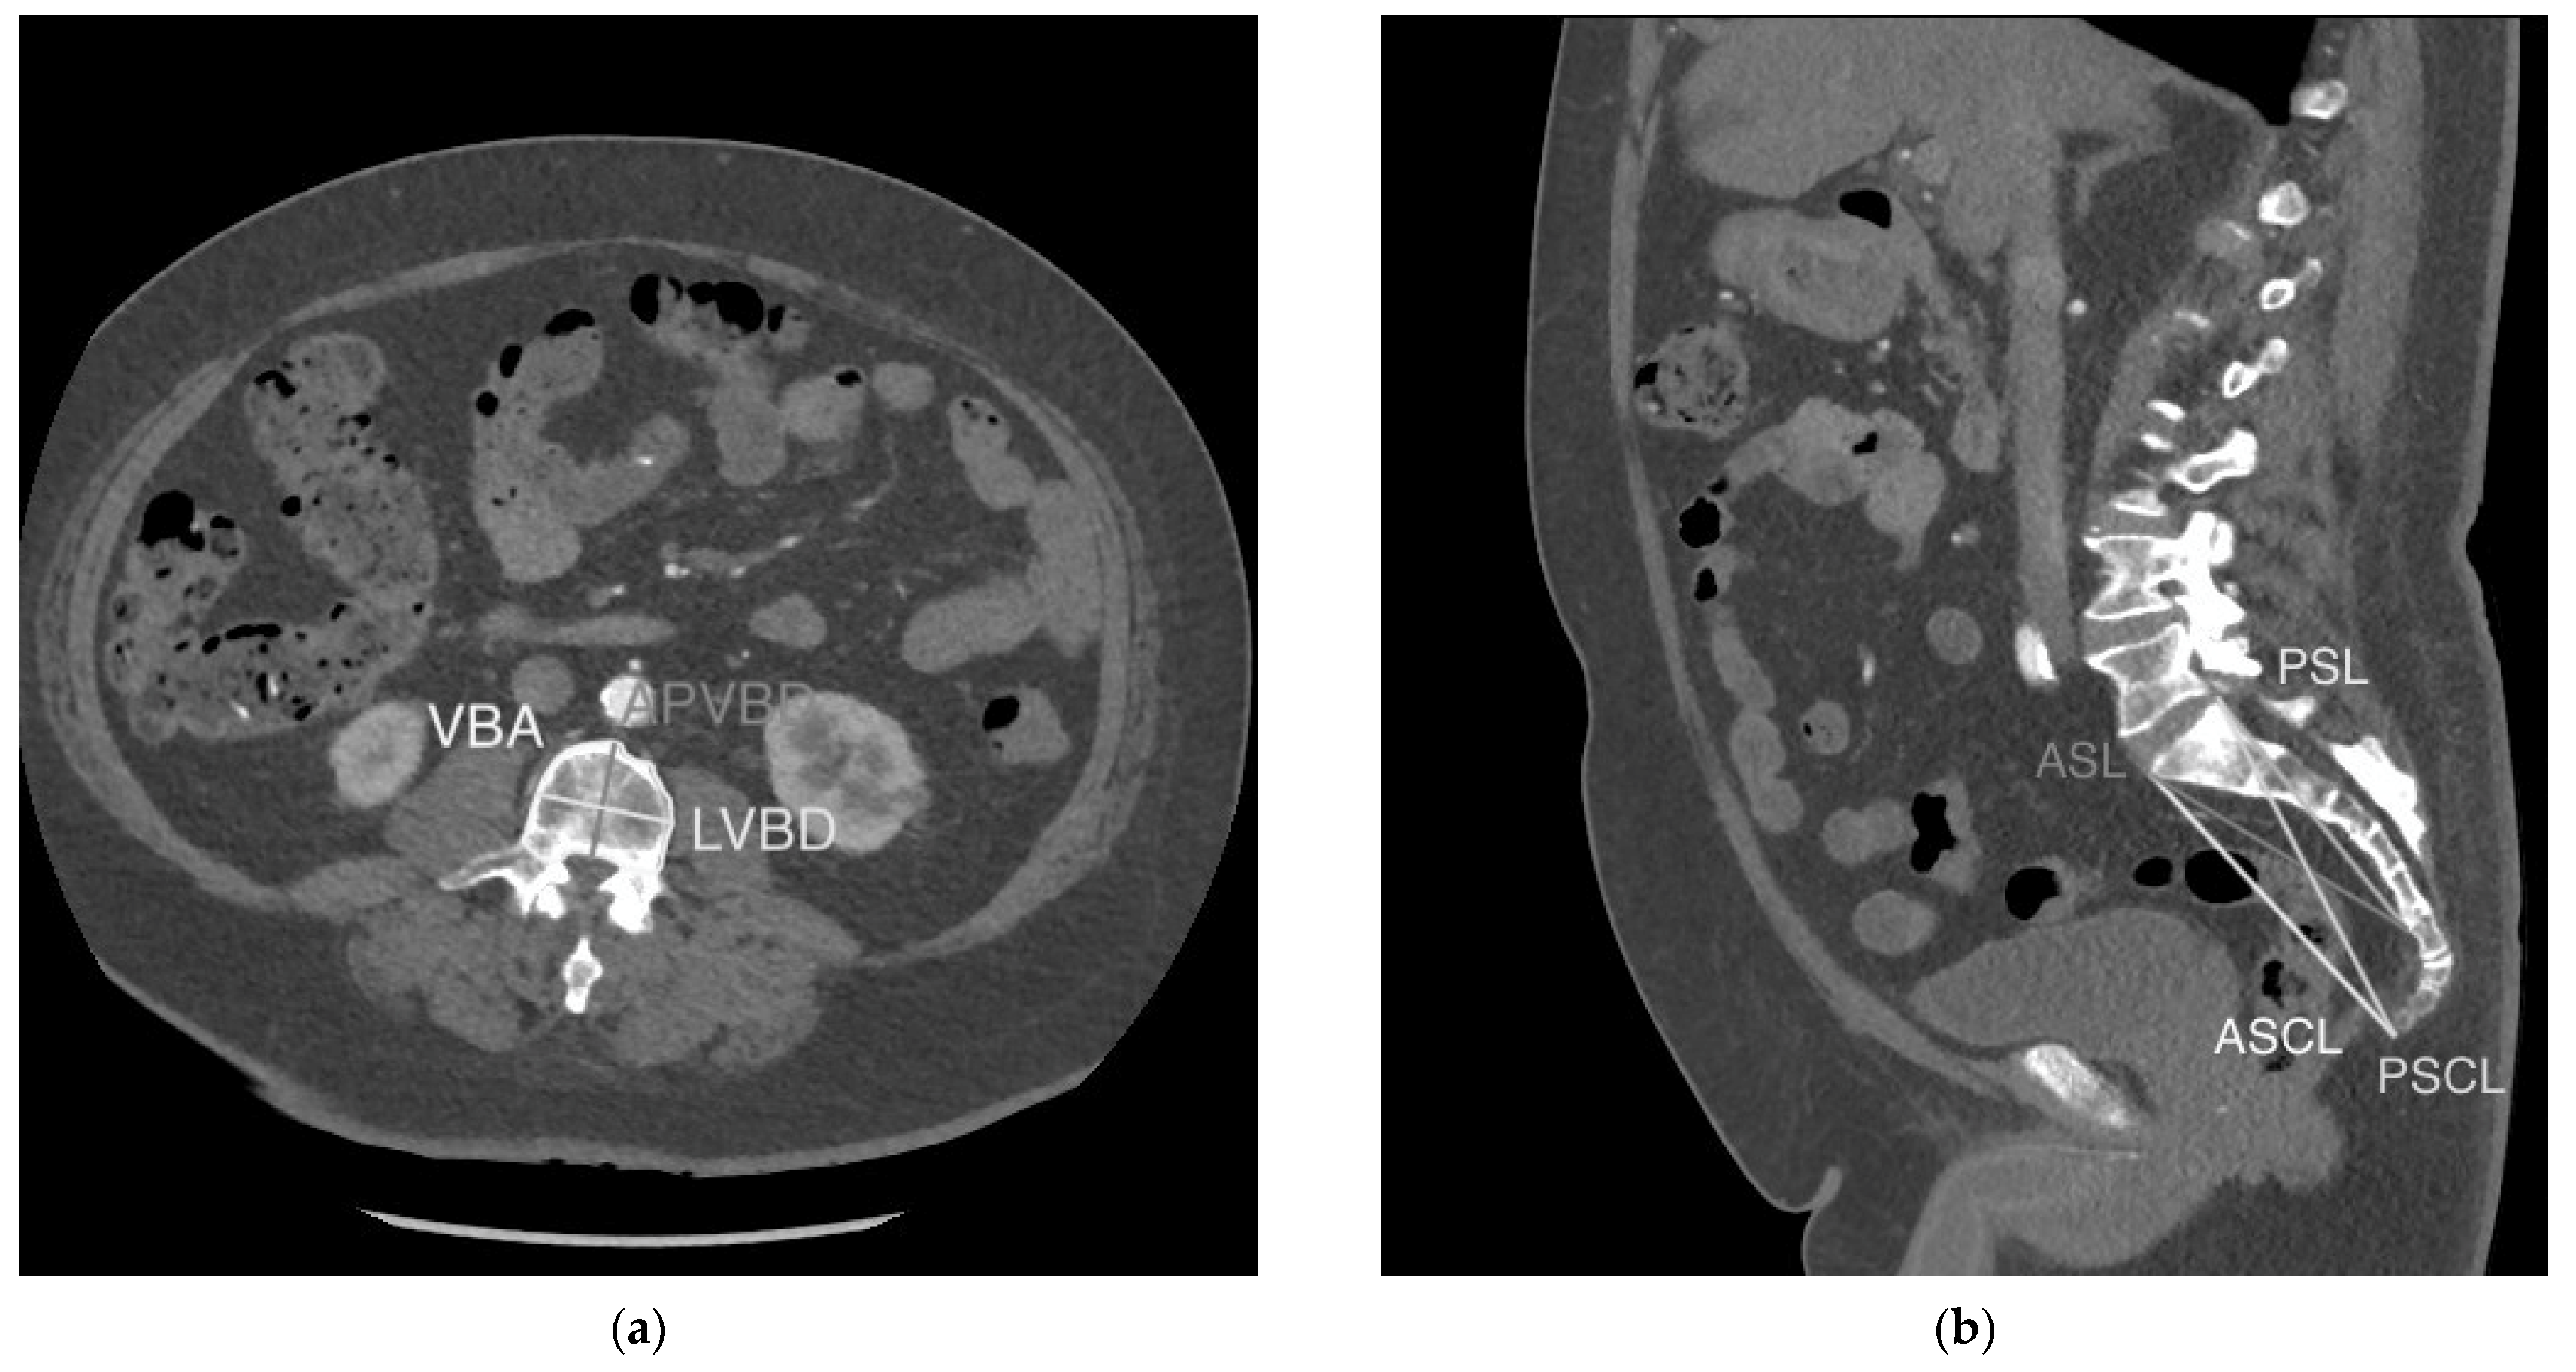

Seven vertebral measurements collected in our study are defined in Table A1 and displayed in Figure 1a,b. They include: vertebral body area (VBA), anteroposterior vertebral body diameter (APVBD), lateral vertebral body diameter (LVBD), anterior sacral length (ASL), posterior sacral length (PSL), anterior sacro-coccygeal length (ASCL) and posterior sacro-coccygeal length (PSCL). VBA, APVBD and LVBD were measured at both the 3rd and 4th lumbar vertebrae using the method previously outlined by Waduud et al. [10]. ASSL, PSSL, ASCL and PSCL were measured according to the method outlined by Torimitsu et al. [11]. Vertebral measurements were taken and recorded on an electronic worksheet by a trained investigator, supervised by an abdominal radiologist. Waduud et al. have previously demonstrated that trained individuals of varying clinical experience can accurately measure vertebral parameters [15]. The VBA measurement was recorded in squared centimetres (cm2) to the nearest decimal of a centimetre, and all linear vertebral parameters were recorded in millimetres (mm).

Figure 1.

Vertebral measurements. (a). VBA, LVBD and APVBD displayed on an axial section through the superior endplate of L3. (b). ASL, PSL, ASCL and PSCL displayed on a mid-sagittal section through the abdomen/pelvis.